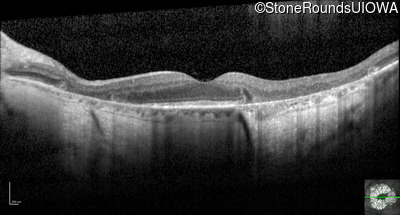

Optical Coherence Tomography - Right - 20/32

Exemplar / OCT Stack

OCT Stack